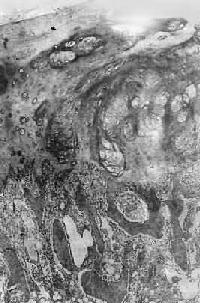

镜下观,肿的分化程度差异很大,分化好的软骨肉在镜下易误诊为软骨,但在肿的边缘可以找到细胞的异型性,如核肥大、深染,出现较多的双核、巨核和多核巨细胞,并可见明显核仁(图17-4)。在分化差的软骨肉则上述细胞的异型性很明显,核分裂像也多见。软骨肉的基质可为与一般透明软骨相似的透明基质,也可为粘液样基质,常见于恶性程度高的软骨肉

图17-4 软骨肉

软骨细胞大小不等,有的较大。许多细胞有肥硕的胞核,有的有双核